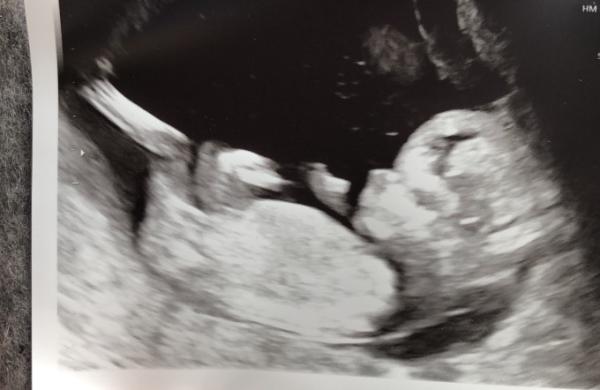

Hallo zusammen Seit einigen Wochen lese ich hier mit und würde mich jetzt doch gern mal vorstellen. Ich bin fast 24, komme aus München und werde das erste mal Mama. Heute beginnt offiziell die 14. Woche, und somit sind wir endlich im 4. Monat Bisher kann ich mich überhaupt nicht über die Schwangerschaft beklagen, es läuft alles so wie es soll. Gestern hatten wir NTM, alles unauffällig und das kleine Wunder ist putzmunter und gesund. Zum Outing konnte meine FA leider nicht viel sagen, zusammen früh meinte Sie, aber plötzlich redete sie nicht mehr von „das Baby“, sondern „ das Mäuschen mag nicht mitmachen“, „ vielleicht dreht sie sich gleich“ Ob das schon was zu bedeuten hat und es ein unauffälliger Hinweis war? Jedenfalls bin ich sehr glücklich, dass es dem Krümel so gut geht. Anbei noch ein Bildchen von „ ihr“ Liebe Grüße an alle und eine schöne Kugelzeit

Bild zu Hallo zusammen ☺️ - Forum für Januar - Mamis